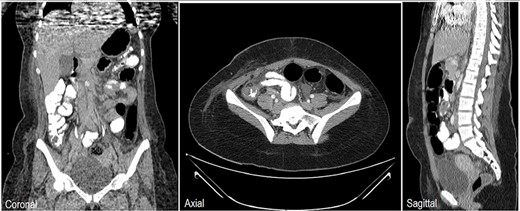

An 18-year-old female patient, with free past medical and surgical history, presented to the emergency department because of abdominal pain of 5-day duration associated with nausea, vomiting, constipation and loss of appetite. The pain was all over the abdomen mostly in the right lower quadrant, of gradual onset, colicky in nature, not radiated with any aggravating or relieving factors. It started intermittently and became continuous with increasing severity on the day of admission. On admission, she had normal vital signs. Physical examination showed a mildly distended abdomen with exaggerated bowel sounds. The patient had abdominal tenderness mostly in the right lower quadrant with abdominal guarding. Rovsing sign and rebound tenderness were both positive. However, the psoas and obturator signs were negative. No scars, hernias or masses were found. Laboratory tests are all within normal. A plain abdominal X-ray demonstrated air-fluid levels of the small bowel, with no pneumoperitoneum (Fig. 1). Abdominal ultrasound showed bowel wall thickening in the ileum, a target-like mass containing a central area of increased echogenicity with a double target appearance. The initial diagnosis was a small bowel obstruction. Because of the severity of the abdominal pain, a decision to proceed with diagnostic laparotomy was made. Nasogastric decompression was done, IV fluids, antispasmodics and antibiotics were started. The patient underwent emergency surgery with a lower midline abdominal incision. Intraoperatively, an intussuscepted segment of the ileum measuring 8 cm in length located 75 cm from the ileocecal valve with dilated proximal ileal and jejunal loops was found and a soft polypoid shape mass was palpable within the lumen (Fig. 2). Enterotomy was performed revealing a tubular segment measuring 6 × 2 × 0.8 cm with a globular swelling at the tip (Fig. 3). No ischemic loop was identified. A diverticulectomy was performed in parallel with the longitudinal axon of the bowel lumen. Ectopic gastric mucosa was identified histologically confirming the diagnosis of inverted MD. The postoperative period was uneventful. CT scan with oral and IV contrast postoperative Day 5 showed no leak from the site of anastomosis (Fig. 4). The patient started a soft diet on Day 5 and was discharged on Day 7.

Chest, abdomen and pelvis CT scan with Oral & IV contrast postop Day 5 showed no contrast leak, no fistula and no obstruction at the site of surgery.